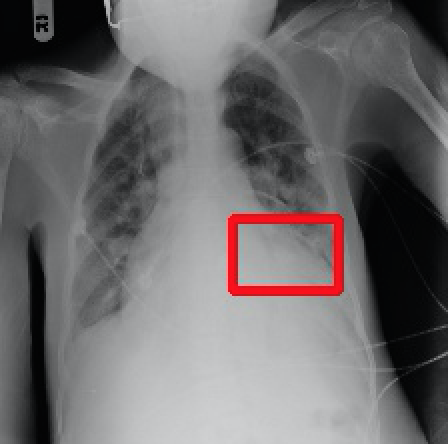

2017年CVPR的一篇“ChestX-ray8”论文[1]首次对医院留存的胸部CT数据库进行人工处理,并通过医学专家分别对8种疾病作标记,形成该领域首个标准的数据库,为胸部医疗的计算机辅助诊断打开了大门,也为后续的研究提供铺垫。CT数据库整理的效果如下图所示,其中红线框内为人工标注的疾病区域:

Atelectasis Cardiomegaly Effusion Infiltrate

Mass Nodule Pneumonia Pneumothorax

图2.1 胸部数据集示例

目前为止,数据集已经达到了14个疾病的分类结果,每张图的大小为1024×1024,少数图片附有由专家标注的病理区域,数据集共有112120张图片,来源于30805个不同的病人,其中51708张图片被标注有疾病,其余则为无病。可以看出无病的数据较多,对有病的特征学习可能较低,相关的学习加速收敛的方法将在2.4节讲解。